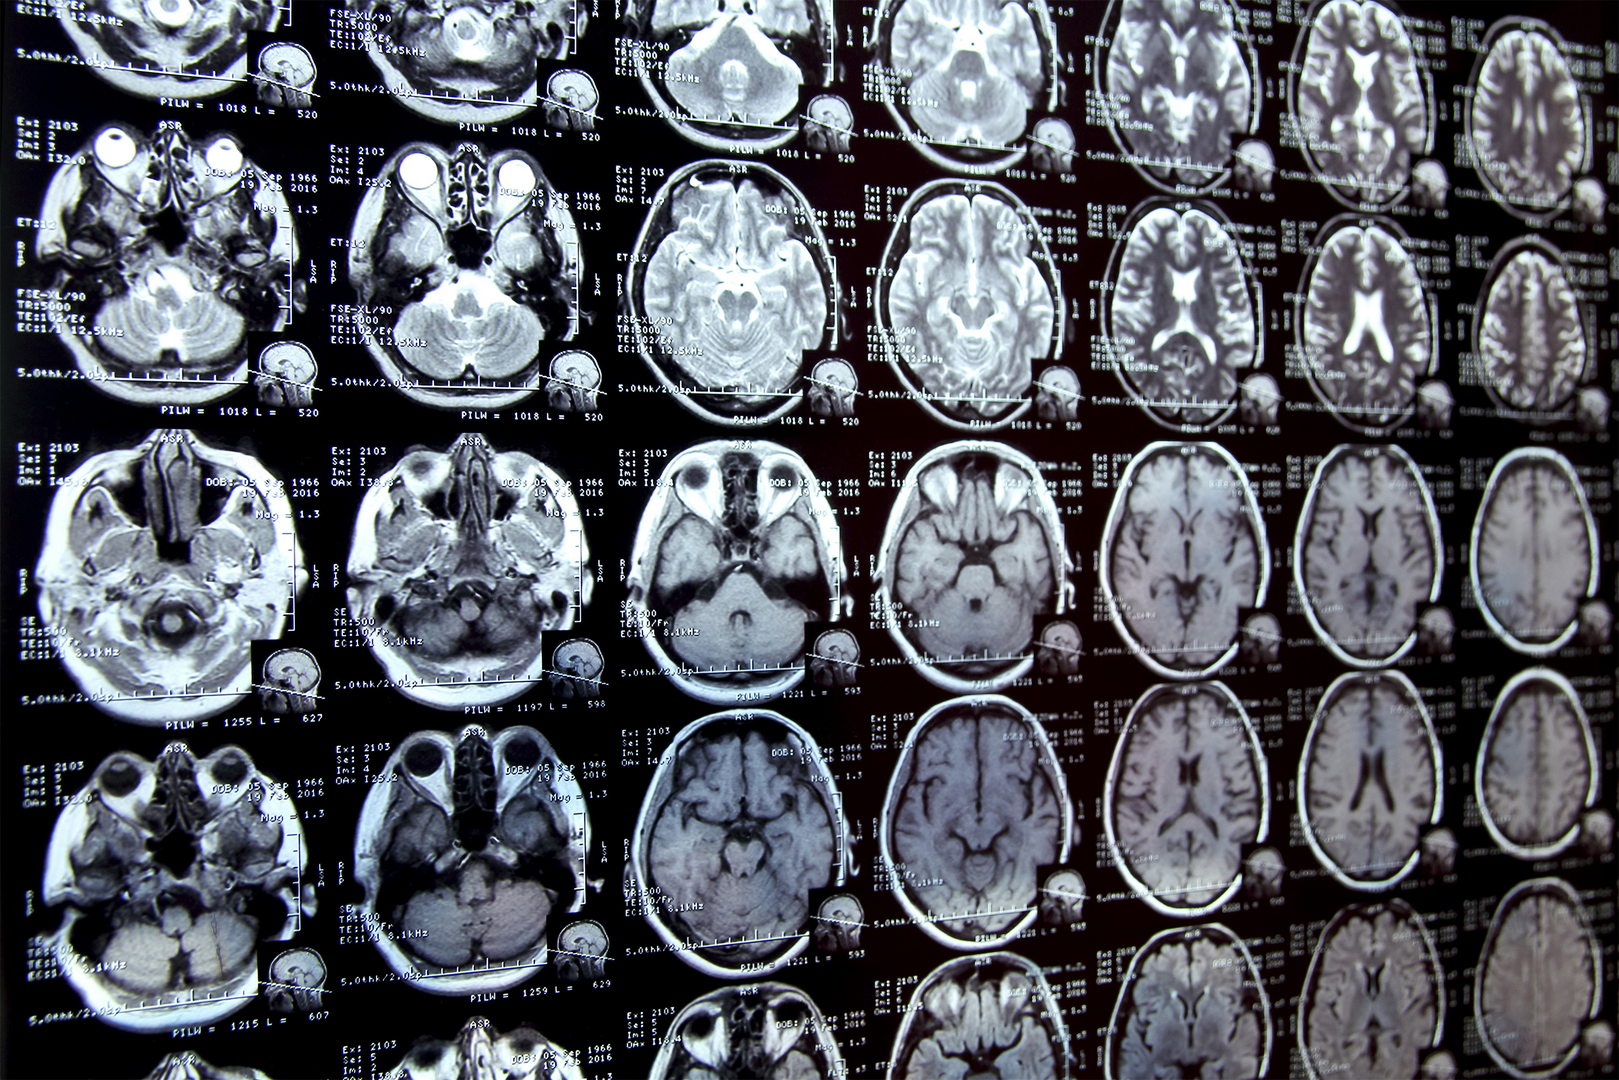

The painstaking process of segmenting – or annotating – specific areas in medical scans plays a critical role in many biomedical research projects. Whether studying changes in brain structures, like your hippocampus, or tracking the progression of a disease, researchers often find themselves laboriously outlining these regions by hand. This method can be particularly grueling, especially when the structures they’re trying to highlight in the complex medical imagery are tough to differentiate.

Imagine what it would be like, for instance, conducting a study on how the brain’s hippocampus changes with age. A researcher would generally need to sift through and painstakingly outline the hippocampus on countless brain scans. Thankfully, a group of researchers from MIT have come up with an exciting solution to this problem.